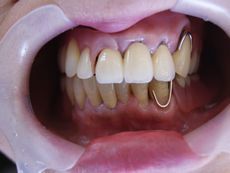

患者さんの左上L123が動揺のため保存不可能でしたので抜歯し、しばらく義歯を使ってもらいながらインプラントを2本埋入し、左上13で上部構造を作った症例です。動揺もなく、インプラントで咬めることを患者さんも喜んでいただきました。

女性 70代

治療の期間・回数:6か月、7回

治療の価格:25円/1歯あたり

治療のリスクや副作用:手術後に、痛みや腫れ、出血、合併症などを引き起こす可能性があります。噛む感覚がご自身の歯と異なる場合があります。見た目がご自身の歯と異なる場合があります。手術後にメインテナンスを継続しないと、インプラントが抜け落ちる可能性があります。